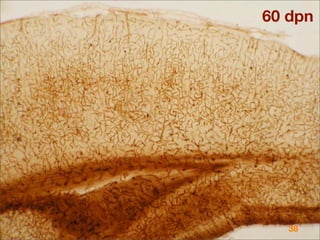

This document discusses blood-brain barrier (BBB) permeability and regulation. It describes the cellular components that make up the BBB, including endothelial cells, astrocytes, pericytes, and the mechanisms that control permeability, such as tight junctions between endothelial cells. It also discusses how BBB permeability is altered in various pathological conditions like stroke, trauma, infection, and neurodegenerative diseases.